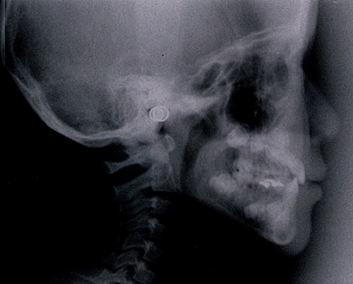

同じ患者様の矯正治療終了後の骨格です。

不安定に見えていた咬み合わせが、反対咬合が改善されて安定して咬みあっていることが分かります。小学校低学年の治療であれば早期治療により反対咬合は容易に改善可能で、骨格の変化を考えてみても反対咬合は早期治療の効果が得られやすい症例と言えます。

次に骨格で比べて診ましょう。

7歳 治療終了時 女子の受け口の骨格です。

同じ人の1年後の骨格です。

小学校低学年の治療であれば、この変化は普通に起こる変化です。

骨格のことからも受け口は早期治療の効果が得られやすい症例です。